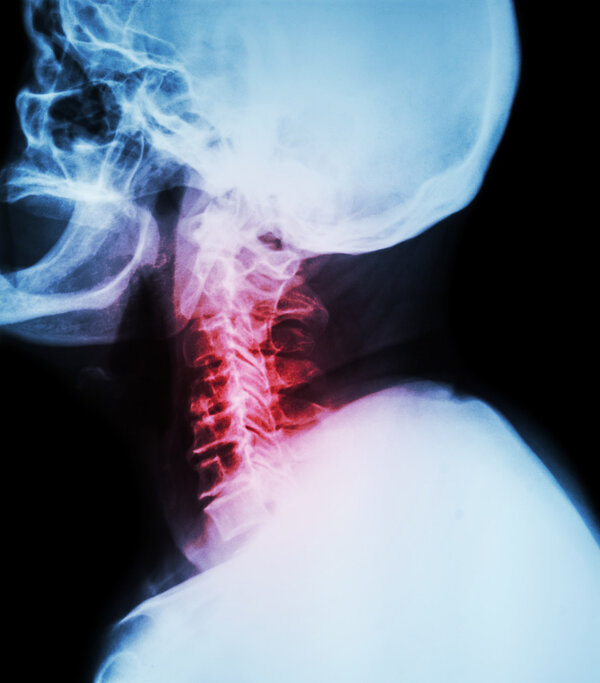

颈椎盘颈椎盘突出怎么治

颈椎盘突出可以考虑采取非甾体抗炎药、物理疗法、神经阻滞、椎间孔扩大术、颈椎前路减压融合术等方法进行治疗。